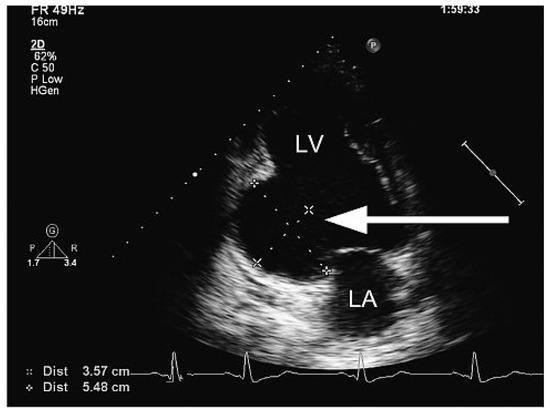

A Case of Infective Endocarditis Caused by Bartonella Quintana: Prolonged Mild Symptoms and a Sudden Life-Threatening Complication

by Florian S. Schoenhoff, Friedrich S. Eckstein, Stefan Zimmerli and Thierry P. Carrel

Cardiovasc. Med. 2009, 12(11), 315; https://doi.org/10.4414/cvm.2009.01455 - 13 Nov 2009

The morbidity and mortality associated with infective endocarditis can be significantly reduced by early diagnosis and initiation of effective therapy. Due to the often nonspecific prosaic symptoms associated with infective endocarditis, patients are likely to seek initial medical care from their primary care [...] Read more.

The morbidity and mortality associated with infective endocarditis can be significantly reduced by early diagnosis and initiation of effective therapy. Due to the often nonspecific prosaic symptoms associated with infective endocarditis, patients are likely to seek initial medical care from their primary care physicians. The authors present the history of a patient suffering from indolent prolonged illness with moderate fever who developed painless macrohematuria and triple valve endocarditis with Bartonella quintana. This pathogen is a gram-negative bacterium responsible for the epidemic louse-borne trench-fever seen in Europe during World War I and particularly seen as an infectious agent in HIV patients. Full article